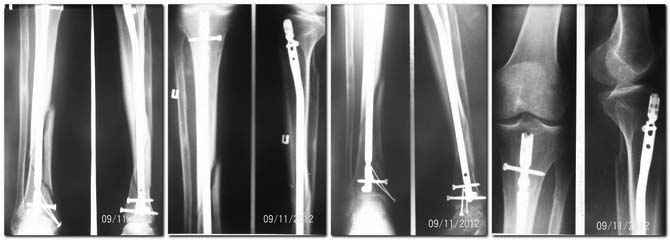

Уважаемые коллеги! Около полугода назад БИОС большеберцовой кости и синтез внутренней

лодыжки. Динамизация через 2,5 месяца. Р-граммы после синтеза, динамизации и на данный

момент. Пациенту 56 лет, соматически сохранен, послеоперационный период без осложнений,

признаков инфекции нет. Ходит с 50%-й нагрузкой, отмечается боль в зоне перелома при полной

нагрузке на оперированную конечность. Поделитель опытом, помогите определиться с

дальнейшей тактикой лечения пациента.